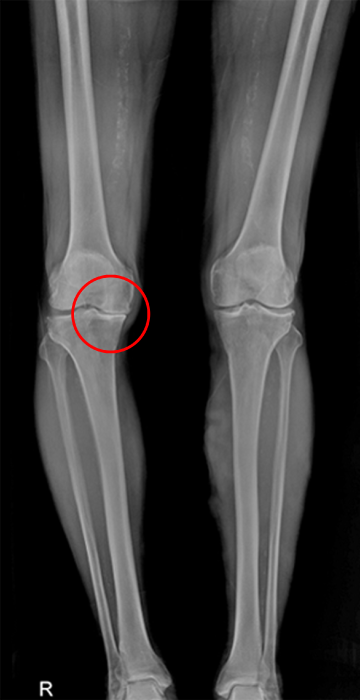

퇴행성 관절염

관절염은 무릎 관절을 보호하고 있는 연골의 손상이나 노화로 인한 퇴행성 변화로 인해 연골이 닳아 없어지는 질환입니다.

관절염은 나이가 들며 누구에게나 발생할 수 있는 질환으로, 특히 무릎의 경우 몸의 하중의 많은 부분을 부담하고 있는 부위로 퇴행성 관절염이 가장 흔하게 발생되는 부위입니다.

정상

퇴행성관절염

(관절의 간격이 좁아져 맞닿아있음)